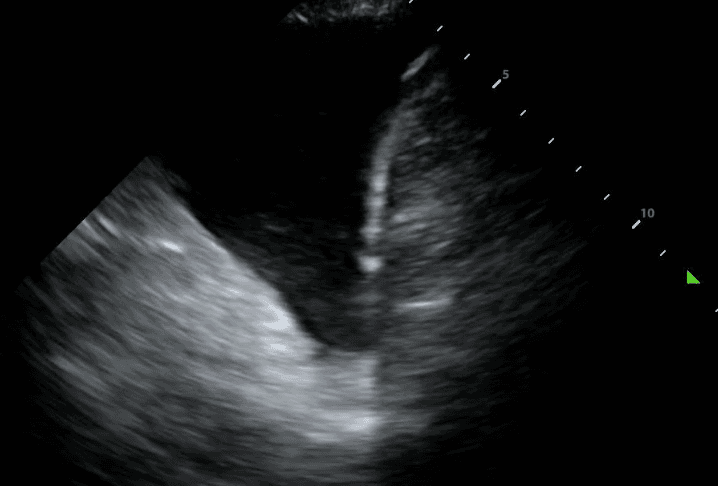

TB can lead to the accumulation of fluid in the pleural space, resulting in a pleural effusion. The incidence of these effusions range from 3% to 30% depending on the prevalence of TB and comorbidities such as HIV. On lung ultrasound, pleural effusion typically appears as anechoic (black) or hypoechoic (dark) fluid collection between the lung and the chest wall. The presence of pleural effusion in TB may indicate complications such as pleural TB or concurrent bacterial infection.